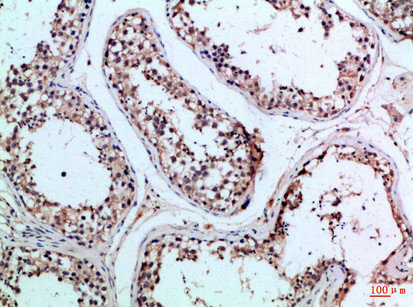

Immunohistochemical analysis of paraffin-embedded Human-testis, antibody was diluted at 1:100